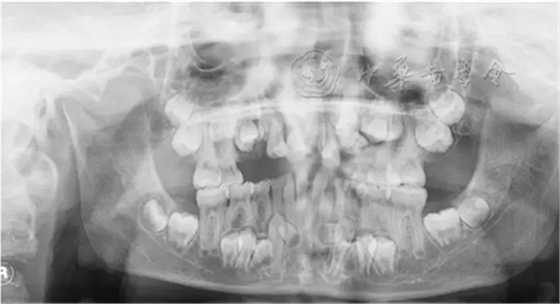

(1)疾病定義及口腔表現(xiàn):是一種罕見的以顱骨和鎖骨發(fā)育不良為主要特征的先天性骨骼系統(tǒng)發(fā)育異常綜合征,又稱Marie-Sainton綜合征,多為常染色體顯性遺傳?;颊呖杀憩F(xiàn)鎖骨單側(cè)或雙側(cè)缺如,顱骨短大,囟門和顱縫寬、延遲閉合或不閉合,面骨較小,眼距寬,鼻梁塌陷。口腔表現(xiàn)為腭蓋高拱,部分患者表現(xiàn)為腭裂或腭黏膜下裂。乳牙萌出正常,除第一恒磨牙和其他個(gè)別牙外,多數(shù)恒牙不能正常萌出,影像學(xué)檢查可見牙胚發(fā)育遲緩,乳牙根吸收遲緩,頜骨內(nèi)埋伏多顆額外牙(圖3)。有些癥狀較輕的患者可只表現(xiàn)為牙齒發(fā)育異常。

圖3 10歲顱骨鎖骨發(fā)育不全患兒曲面體層X線片,可見頜骨內(nèi)多顆埋伏額外牙,恒牙胚發(fā)育遲緩,恒牙萌出障礙